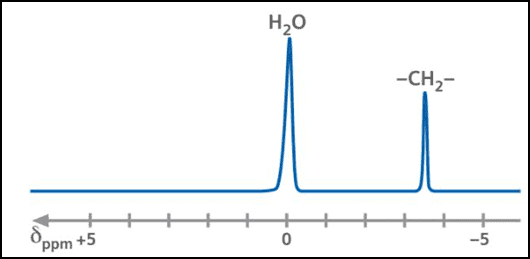

Dixon脂肪抑制技术是由Dixon 提出,其基本原理是利用水、脂肪的化学位移差异,使用不同的回波时问,分别采集水和脂肪质子的in Phase 和 opposed -phase两种回波信号。

当水和脂肪相位相同时,采集到的信号为:

S1=W + F;

当水和脂肪相位相反时,采集到的信号为:

S2=W – F;

两种不同相位的信号相加:

S1 + S2 =2W;

即可以得到去除脂肪信号,产生一幅纯水质子的图像,从而达到脂肪抑制的目的。

两种信号相减:

S1 – S2 =2F;

也可以得到纯脂肪的信号,产生脂肪图像;

这就是原始的两点式Dixon方法,还有多种扩展形式,以及三点式Dixon成像方法。